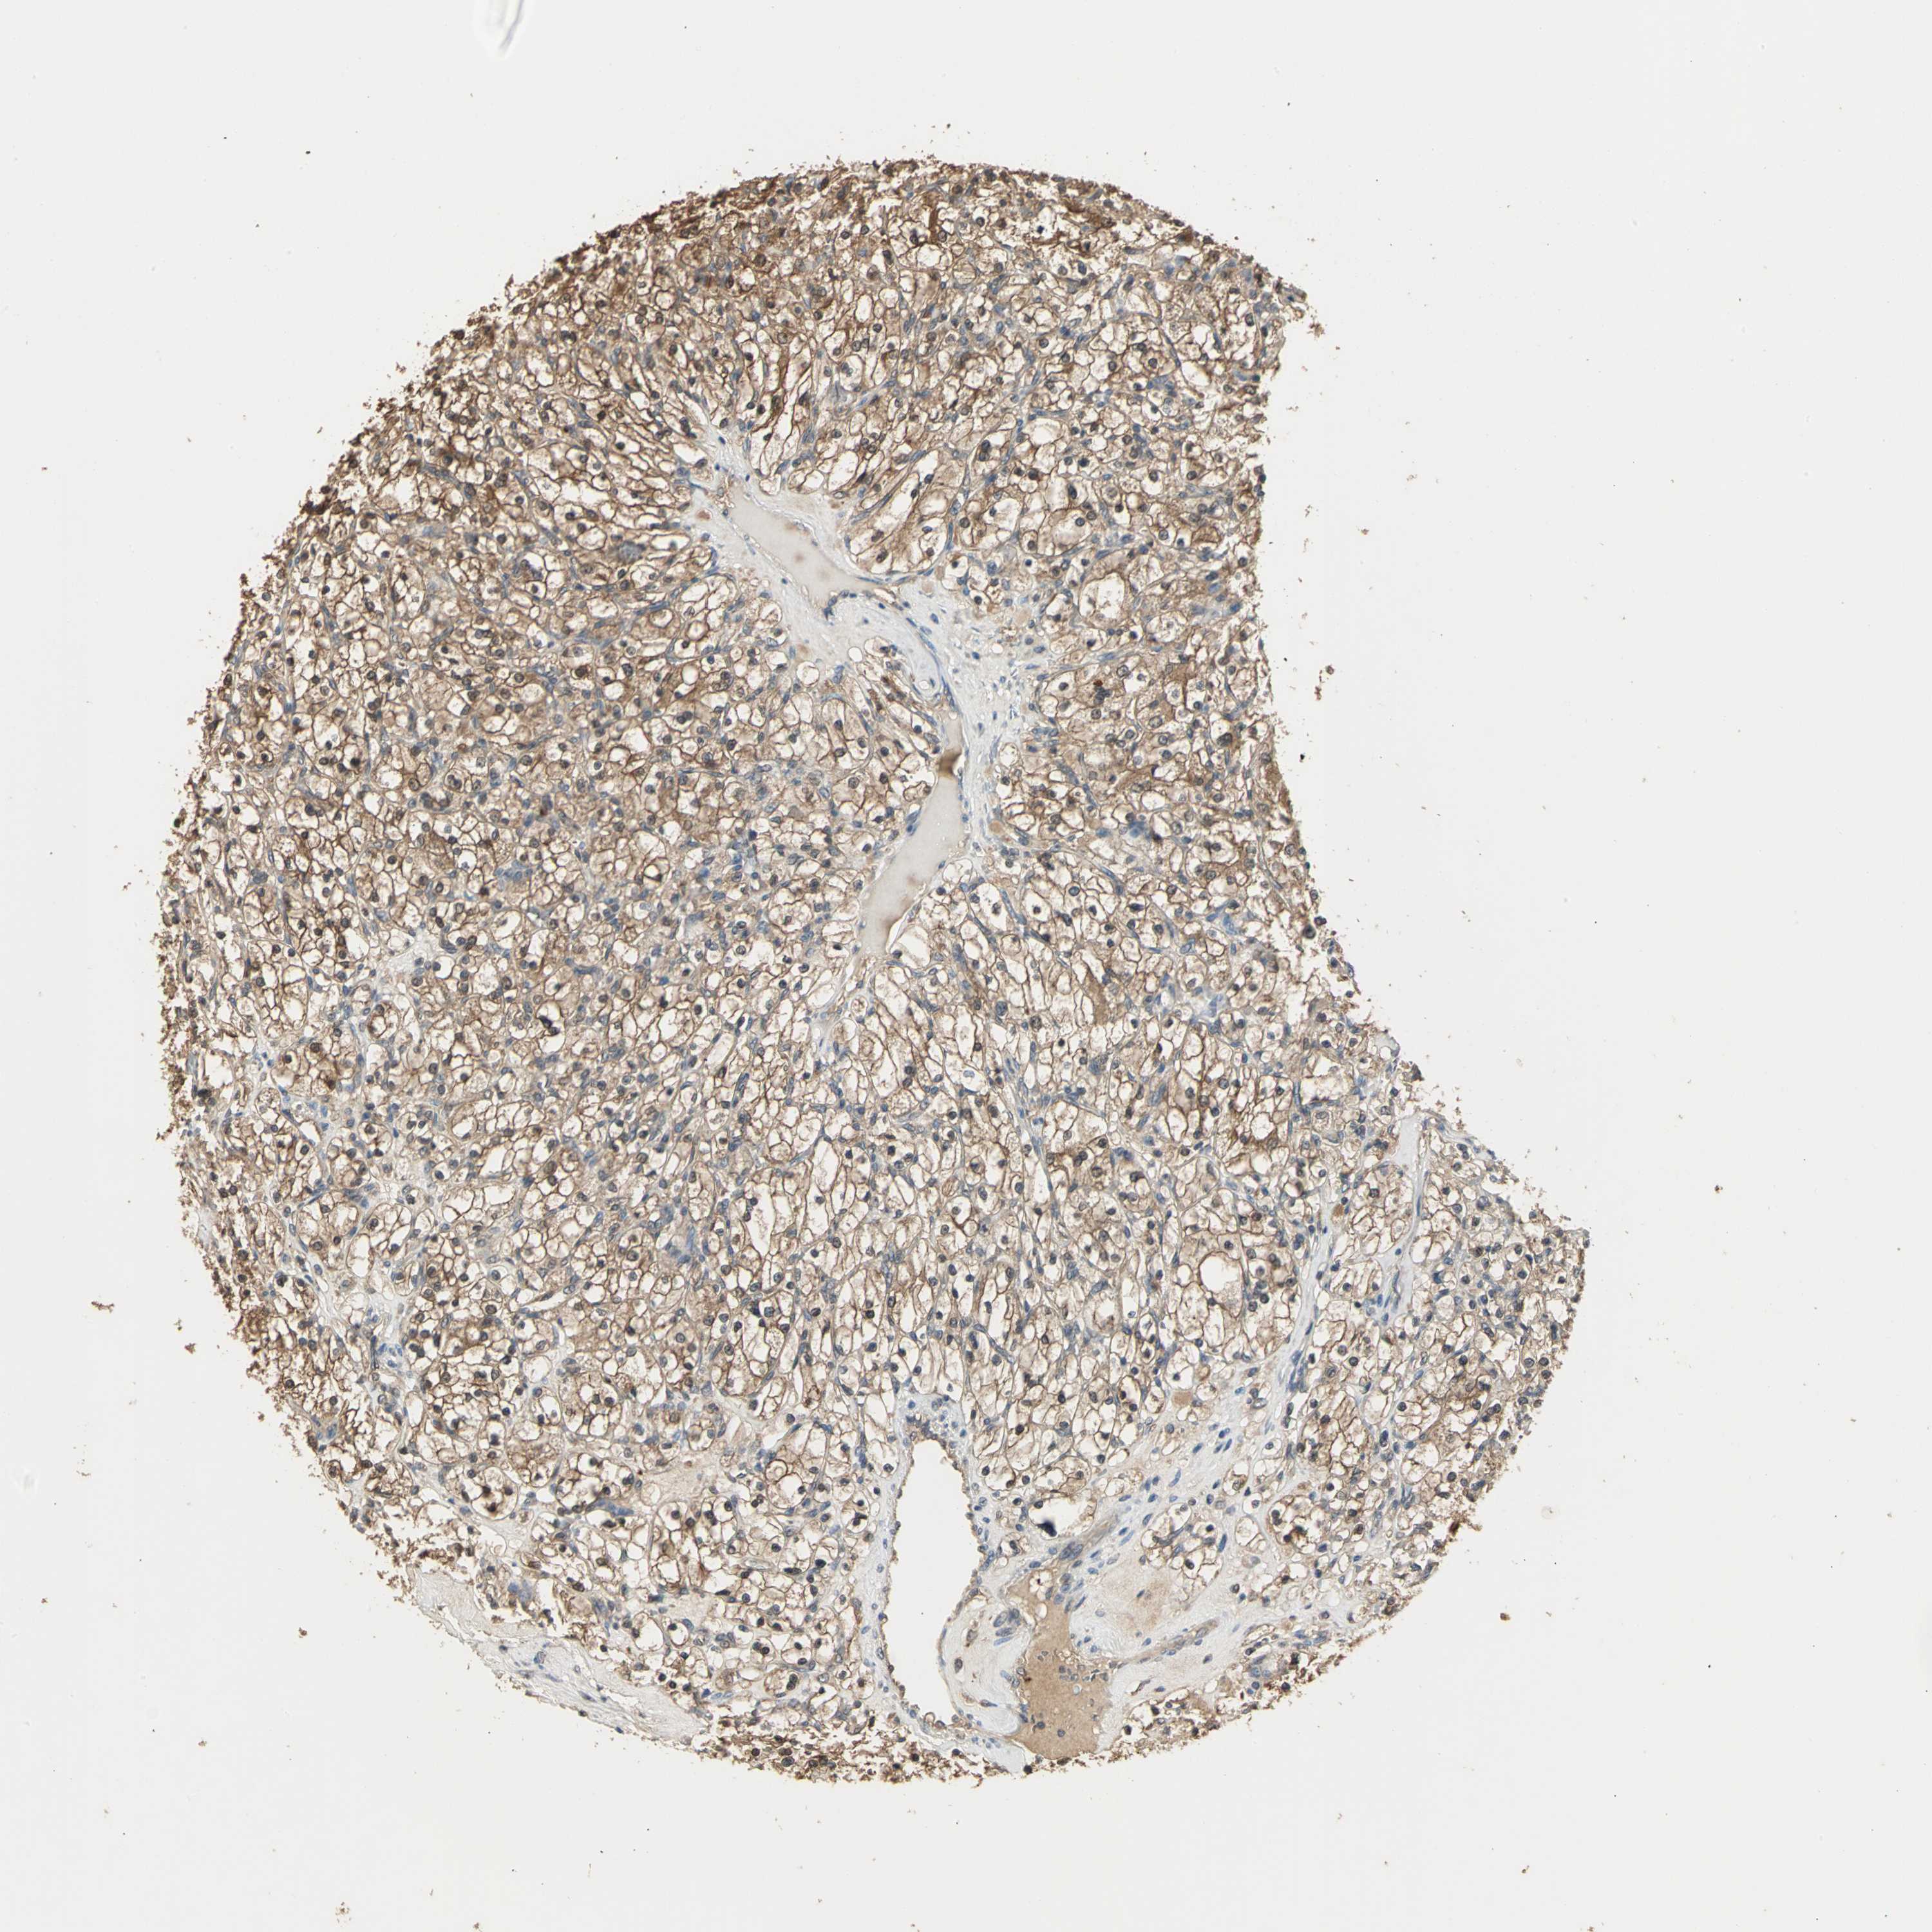

CANCER RENAL CANCER Show tissue menu